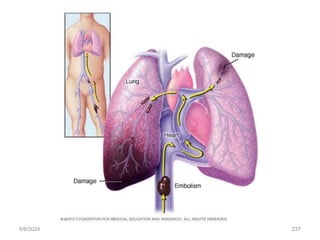

PLEURAL EFFUSION

Pleural effusion, a collection of fluid in the pleural space, is rarely a

primary disease process but is usually secondary to other diseases.

Normally, (5 to 15 mL), which acts as a lubricant

Pleural effusion Cause

• heart failure, TB, pneumonia, pulmonary infections (particularly

viral infections),

• nephrotic syndrome, connective tissue disease, pulmonary

embolism, and neoplastic tumors.

• Bronchogenic carcinoma is the most common malignancy

Pathophysiology

The effusion can be composed of a relatively clear fluid, or it

can be bloody or purulent.

An effusion of clear fluid may be a transudate or an exudate